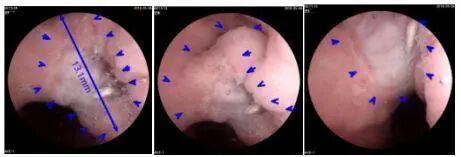

病例一: 史女士,38岁,2018年5月6日前往体检中心正常查体,病历显示:无家族史、既往史,1周前持续腹痛4天,自行缓解,现无明显不适。磁控胶囊胃镜查体结果显示为疑似胃癌,后经病理确诊为(胃角)低分化腺癌。

病例三: 曹女士,45岁,2017年10月13号前往医院体检中心正常查体,使用胶囊胃镜查出胃癌,经病理诊断为腺癌。